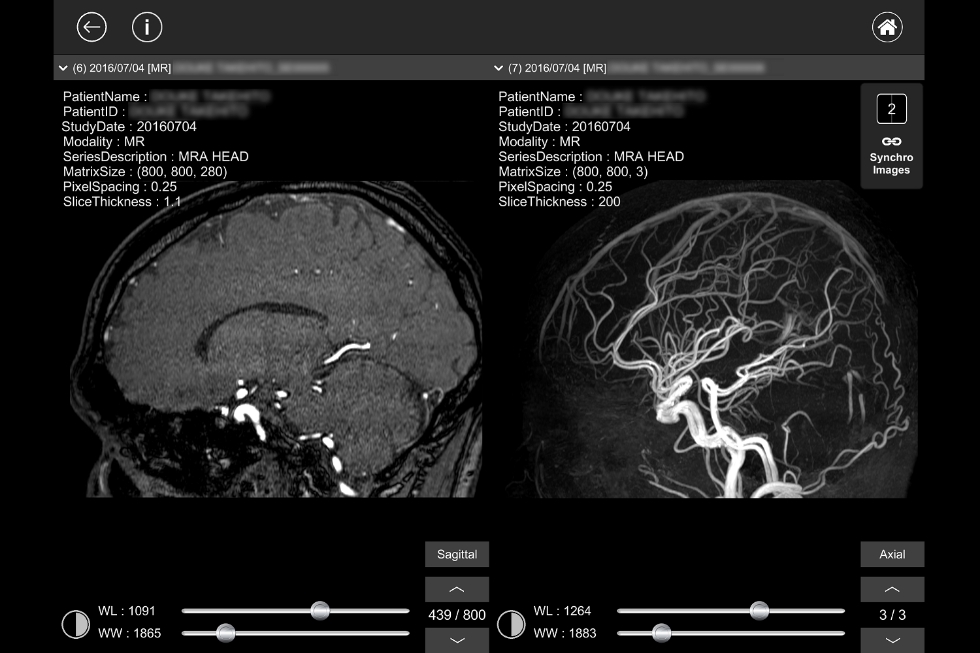

MR、CT、SPECT、PET等で撮影されたDICOM画像を高速で読み込み、直感的に画像を確認頂けます

デュアル画面機能

デュアル画面機能により、二つの画像を簡便に比較するができます